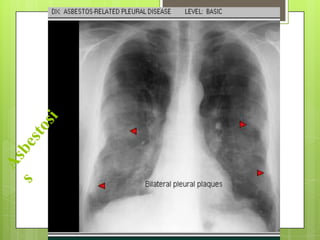

ASBESTOSIS

 Asbesto: silicato mineral fibroso natural

(amianto), gran capacidad de aislamiento y

resistencia al calor, acidosis, álcalis,

revestimiento de cañerías, frenos y material

de techado. El mas utilizado: crisolita.

 Mas expuestos: industria de fibrocemento, textil,

naval, automotriz y trenes

 Neumoconiosis producida por inhalación de

fibras de amianto dando fibrosis pulmonar

intersticial lenta y progresiva (>15-20 años)

RADIOGRAFÍA Y ESPIROMETRÍA

 Imágenes lineales en campos inferiores y

engrosamiento de pleura parietal 

calcifican (>20 años)